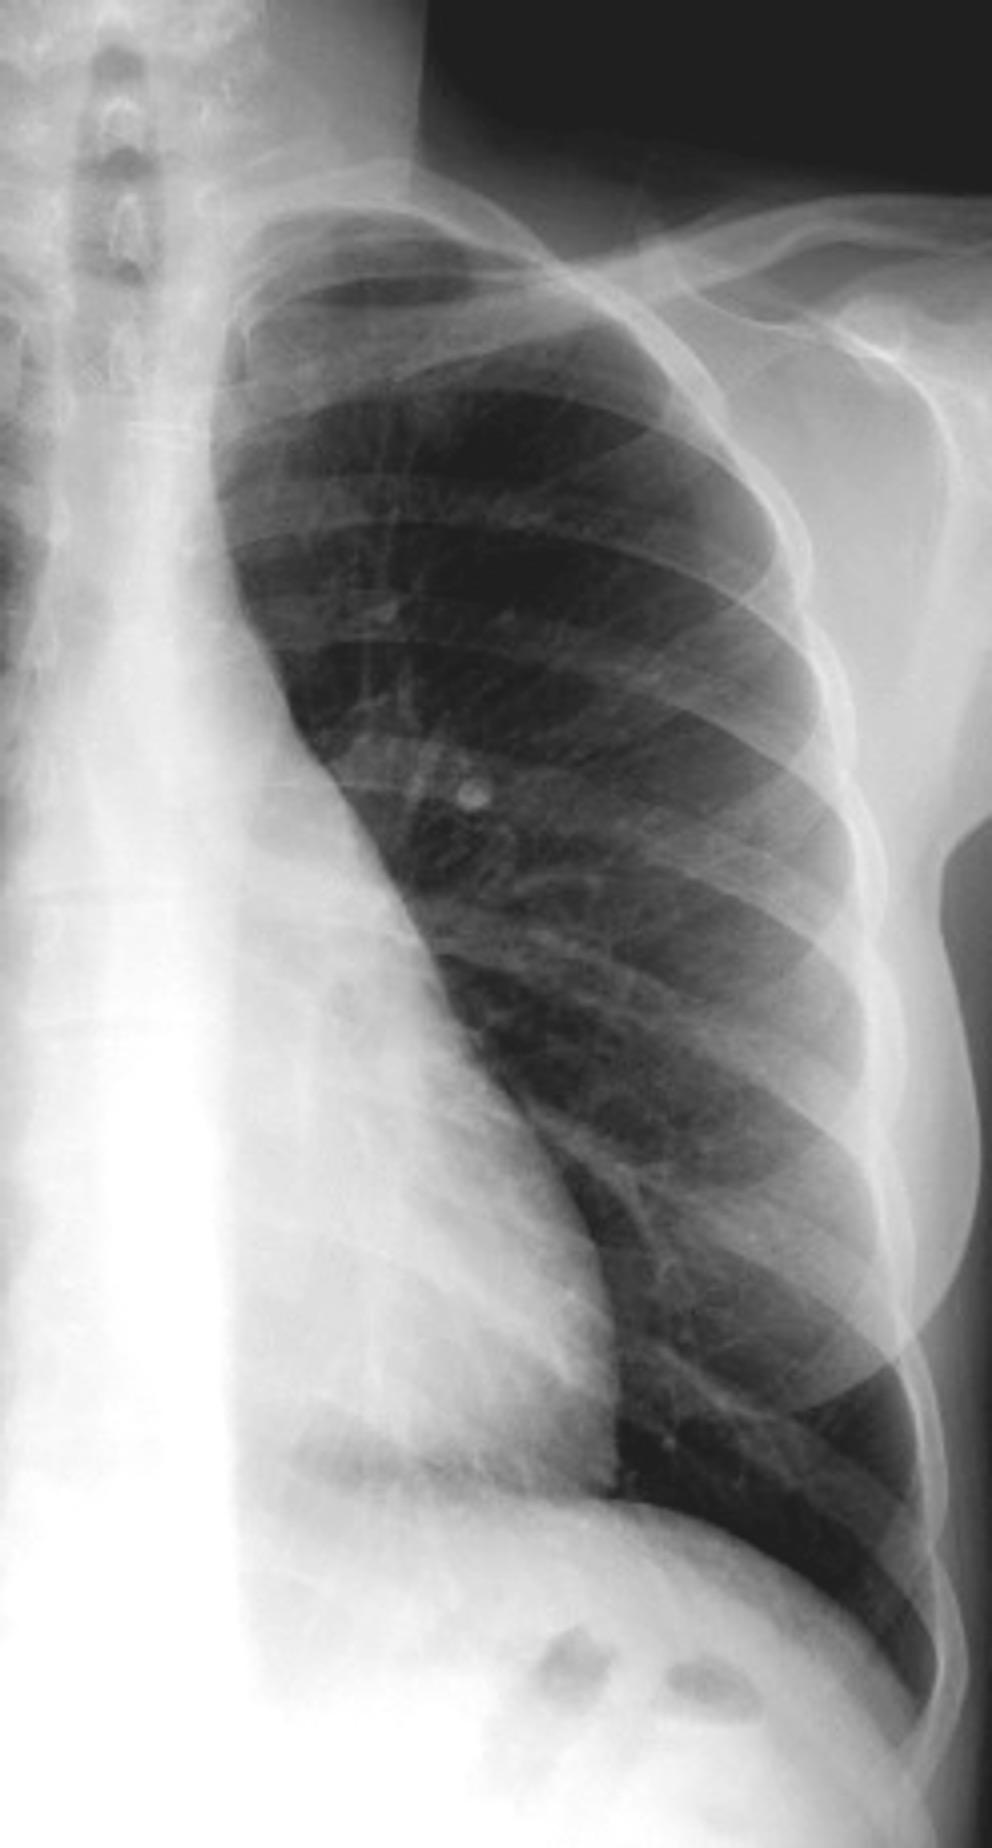

25. ELEVACIÓN UNILATERAL. TEP

Tromboembolismo pulmonar Diafragma elevado 20%

Atelectasia crónica de LLI en paciente con enfermedad neuromuscular.